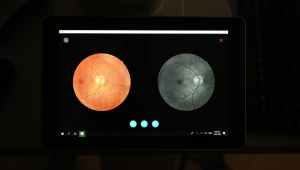

Порівняння зображень

Користувачі можуть обирати різні періоди або ракурси знімків для порівняння.

Функція монтажу

NFC-700 надає лікарям можливість працювати з кількома зображеннями, щоб ширше бачити сітківку пацієнтів.